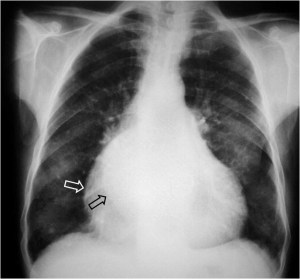

SIGNO DEL TERCER MOGUL

El signo del tercer mogul se refiere a la lobulación anormal del contorno mediastínico izquierdo entre la arteria pulmonar y el ventrículo izquierdo. Pueden producir esta lobulación lesiones cardíacas y pericárdicas (orejuela izquierda aumentada, aneurisma ventricular o de la arteria coronaria, quiste o masa pericárdicos, etc) y también algunos tumores mediastínicos, como timomas. En la imagen, el signo corresponde al crecimiento de la orejuela izquierda (flecha roja) en un enfermo mitral.

La palabra «mogul» es un término utilizado por los esquiadores para describir un acúmulo mamilar de nieve compacta en una ladera montañosa.

El primer mogul corresponde al cayado aórtico (flecha blanca); el segundo, a la prominencia de la arteria pulmonar (flecha roja); y el cuarto, al contorno del ventrículo izquierdo (flecha negra).